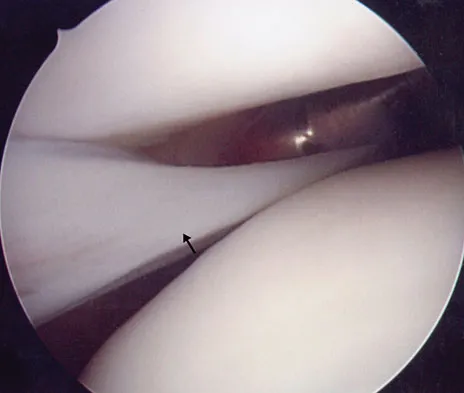

A football player sustains a traumatic anterior inferior dislocation of the shoulder in the last game of the season. It is reduced 20 minutes later in the locker room. The patient is neurologically intact and has regained motion. If the patient undergoes arthroscopic evaluation, what finding is seen most consistently?

Explanation